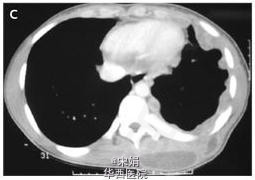

18岁男性,因左侧背部肿物进行性长大6月来诊。既往史无特殊。就诊3天前,患者左外侧胸壁疼痛处流出浆液样液体,CT示胸部多个胸膜结节包绕左肺,背部肌肉间可见大量液体积聚,与脓胸破溃处相符,脓液自此从胸壁流出。胸膜活检培养阴性,脓液培养结核分枝杆菌阳性,HIV(-)。患者结核杆菌对抗结核药物敏感,后接受标准抗结核治疗,病情逐渐好转。自溃性脓胸为结核脓胸的常见并发症,结核性脓胸的壁层胸膜破裂,排出内容物,经过胸腔,进入胸壁皮下组织。CT可显示胸腔内外的病变,可呈厚壁的包裹性积液,还可显示两者之间的瘘道。